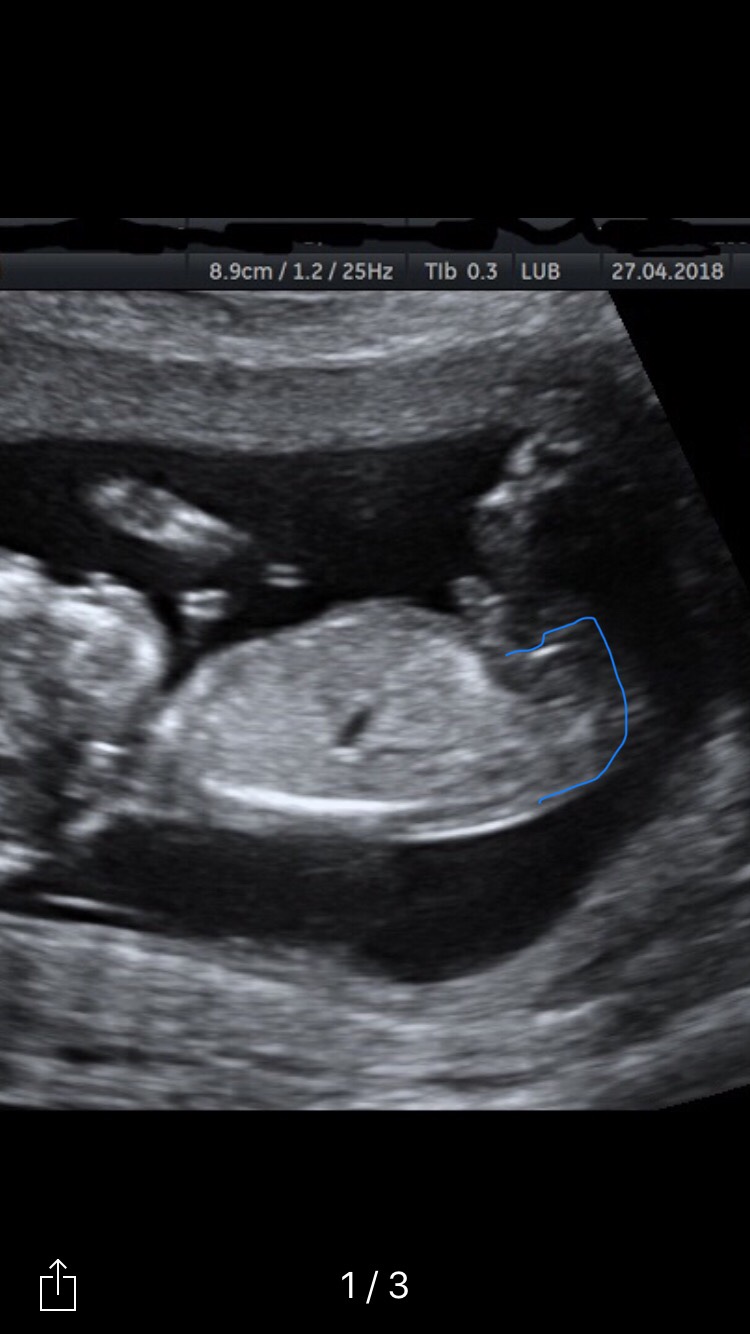

Hi all, would appreciate any guesses. Thanks in advance.

Girl guess

My guess is slightly boy based on skull. Not sure I see a nub

Maybe boy. Really not the best nub pics unfortunately. Congrats on your little one!

Agree maybe boy

VERY tentative pink lean based on the top pic. But it's a bit early for me still and they're not the best shots. Precious little one!!

This ist how I am seeing the nub, I‘m seeing a little penis forming.

Boy guess. I think I see a stacked nub in your 3rd photo!